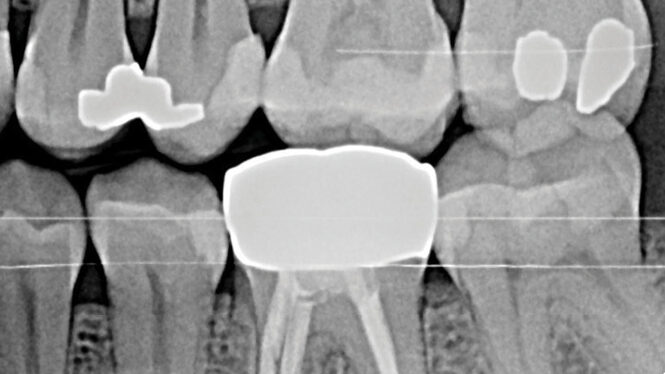

PG-Fig1b alternate text for this image